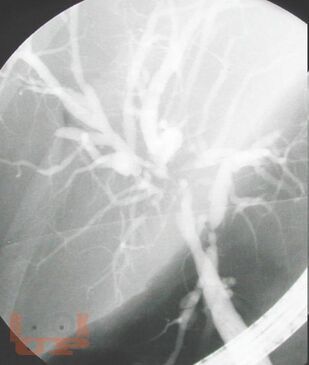

Методы диагностики механической желтухи

Методы диагностики механической желтухи : Учебно-методическое пособие / М. А. Агеев, Д. А. Славин, А. Н. Чугунов, Л. Е. Славин. - Казань : КГМА, 2018. - 48 c. - Текст : электронный // ЭБС "Букап" : [сайт]. - URL : https://www.books-up.ru/ru/book/metody-diagnostiki-mehanicheskoj-zheltuhi-16058875/ (дата обращения: 30.04.2026). - Режим доступа : по подписке.

Неотложная хирургия - одно из наиболее актуальных, сложных и ответственных направлений хирургии. Пациенты пожилого и старческого возраста с механической желтухой различной этиологии толстой кишки составляют значительный контингент, госпитализируемый в хирургические стационары по экстренным показаниям. Издание реализовано с учетом опыта сотрудников кафедры и современных представлений о патогенезе, методах эндоскопической диагностики, клинических проявлениях и основных принципах лечения больных синдромом механической желтухи, обусловленной осложнениями патологии гепатопанкреатодуоденальной зоны и желудочно-кишечного тракта. Успех в лечении таких пациентов во многом зависит от своевременности и точности постановки диагноза.